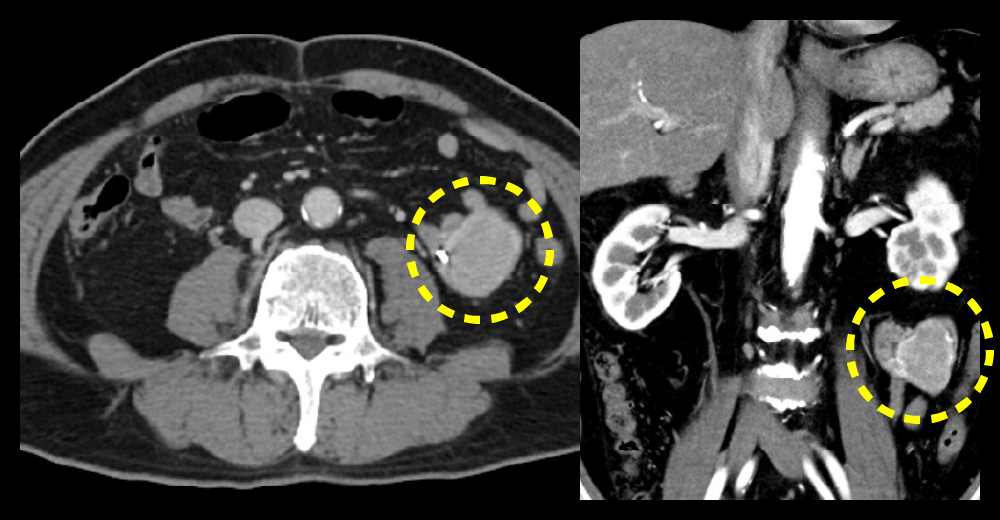

糖尿病の脂肪肝(MAFLD)、肝がんサーベイランスにおける定期腹部エコーで診断された無症状空腸GISTの患者さんです。

無症状空腸GIST 無症状空腸GIST

無症状空腸GIST